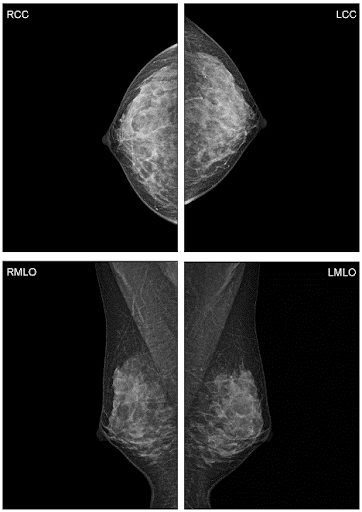

Метод прицельной маммографии с увеличением применяется для более детального исследования определенной области молочной железы. Он отличается высокой точностью диагностики. В отличие от обычной маммографии, которая предоставляет более общую информацию о состоянии молочных желез, прицельная маммография с увеличением позволяет получить точные данные о процессах, происходящих в тканях, благодаря методу компрессии конкретного участка.